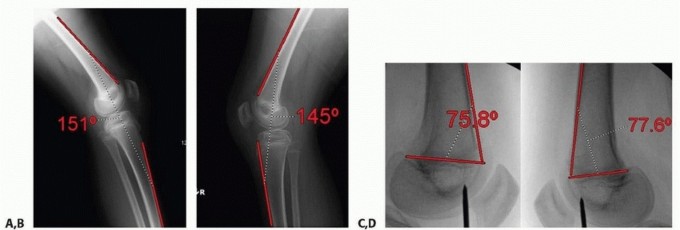

- ###

- FIG 8 • A,B. A 12-year-old boy with spastic diplegia who ambulates with a crouch gait, hamstring contracture, and knee flexion contracture. C,D. Intraoperative fluoroscopy demonstrating preoperative PDFA. The child underwent hamstring transfer and distal femoral guided growth with placement of 6.5-mm cannulated screw positioned anterior in the center of the distal femur. E,F. Postoperative lateral radiographs show improved PDFA and full extension on clinical examination. (Courtesy of UW Pediatric Orthopaedics.)